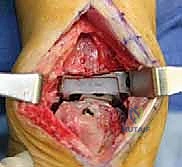

تعتبر غرفة العمليات ساحة لإظهار البراعة الجراحية. عملية المراجعة تستغرق عادة من 3 إلى 5 ساعات وتتم عبر الخطوات المعقدة التالية:

الخطوة الثانية: النهج الجراحي (Surgical Approach)

يتم فتح الشق الجراحي الأمامي القديم بحذر شديد لتجنب إتلاف الأوعية الدموية والأعصاب، وهنا تبرز أهمية تقنيات الجراحة الميكروسكوبية التي يتقنها الدكتور هطيف.

الخطوة الثالثة: إزالة المفصل القديم (Explant Removal)

يتم استخراج المكونات المعدنية والبلاستيكية لمفصل (Agility) القديم بحرص بالغ للحفاظ على ما تبقى من العظم السليم.

الخطوة الخامسة: تركيب المفصل الجديد أو الدمج

يتم إدخال المفصل الجديد المخصص للمراجعة، والذي يحتوي غالباً على سيقان (Stems) تدخل عميقاً في عظمة الساق وعظمة الكاحل لضمان الثبات الميكانيكي. في حال وجود كسور في الكعب، يتم تثبيتها في هذه المرحلة.

الخطوة السادسة: الإغلاق التجميلي

يتم خياطة الأربطة والأنسجة الرخوة والجلد بطرق تجميلية دقيقة لتقليل الندبات وسرعة الالتئام، ثم توضع القدم في جبيرة خلفية واقية.